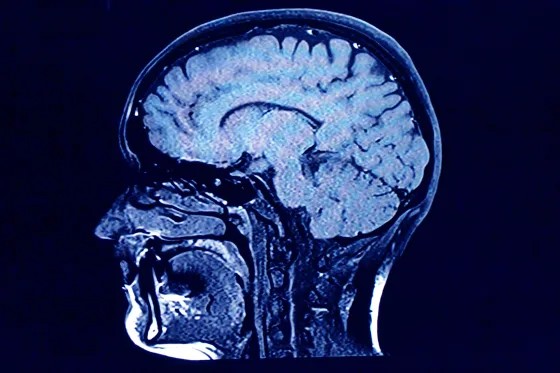

این مطالعه بر اساس اسکنهای MRI انتشار آب در مغز حدود ۳۸۰۰ نفر انجام شد. بر اساس این حقایقی درباره مغز، پنج دوره اصلی با ویژگیهای زیر تعریف میشوند: